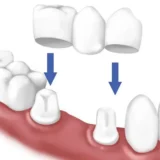

Trong thời đại hiện nay, nhiều người đang tìm kiếm giải pháp để khắc phục tình trạng răng mọc lộn xộn, trong đó bọc sứ được gợi

Răng mọc lộn xộn không chỉ ảnh hưởng đến thẩm mỹ khuôn mặt mà còn gây ra nhiều vấn đề về sức khỏe răng miệng như khó